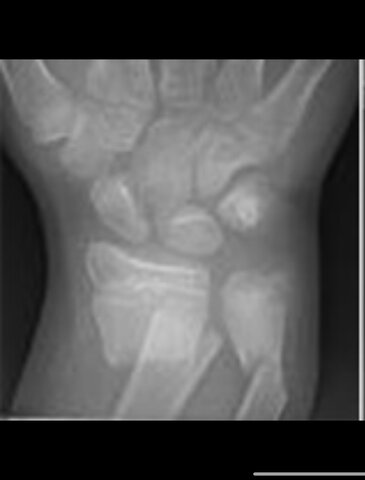

• Radiografía en USA

Radiografía en USA

La primera radiografía en los Estados Unidos fue por la Universidad de Dartmouth a un niño que se fracturo un brazo.